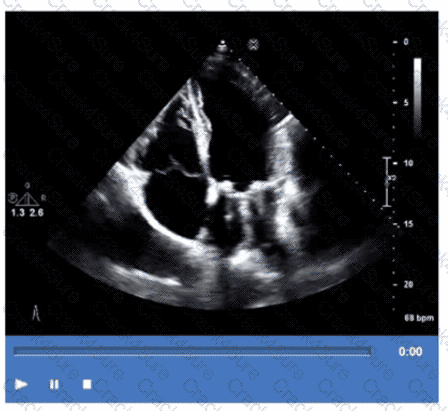

Which is the most likely abnormality represented in these images from a 48-year-old man with shortness of breath?

Which diagnosis is most consistent with the findings in these images?